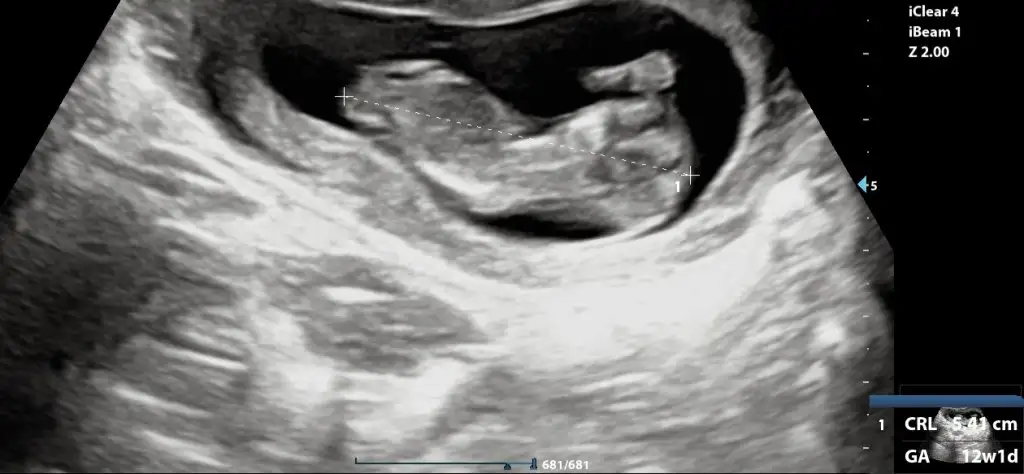

Ben de cok merak ediyorum 12.haftadayim yorumu olan var midir

Eklentiler

• InCollage_20231118_134950662.webp

55,1 KB · Görüntüleme: 104